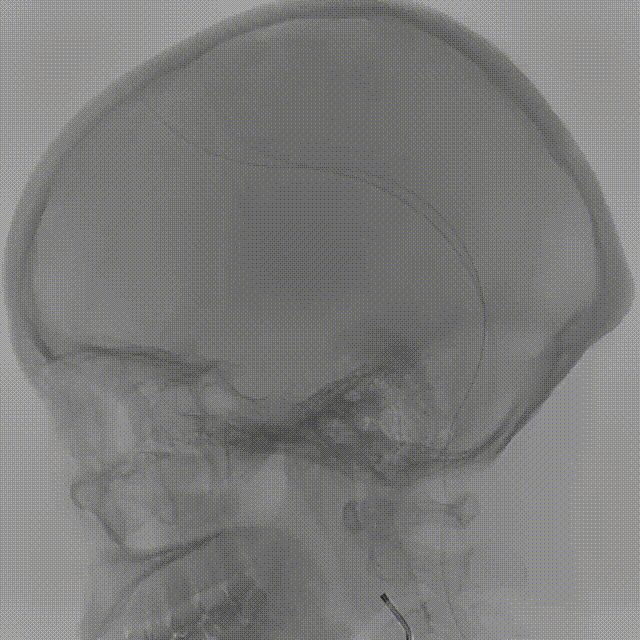

术中DSA造影:右侧颈内动脉正、侧位造影,显示右侧颈内动脉床突旁大型动脉瘤。

术中DSA造影:右侧颈内动脉3D造影提示:右侧颈内动脉床突旁大型动脉瘤,大小约为20.72×16.33mm,远端血管直径1.92mm,近端血管直径3.48mm。